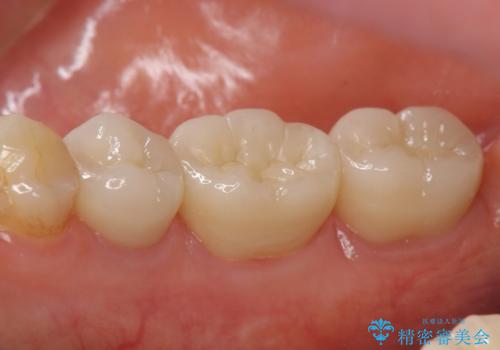

- 右下奥の銀歯3本をオールセラミッククラウンで治療した症例です。

今回用いたオールセラミッククラウンは、ジルコニアフレームという白い素材の上にセラミックを盛っているため審美性が非常に高いのが特徴です。

またジルコニアは人工ダイヤモンドの材料にも使われているほど高い強度を持っており、そのためオールセラミッククラウンは審美性だけでなく、奥歯やブリッジの補綴も可能とするクラウンです。